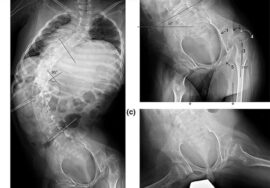

تحسين زاوية كوب (Cobb Angle): بعض الدراسات أظهرت انخفاضًا ملحوظًا في زاوية الانحناء بعد ممارسة التمارين بانتظام.

المتابعة الدورية: تصوير العمود الفقري كل فترة لتقييم التقدم.

متابعة التقدم بالتصوير الدوري للعمود الفقري.

الاعوجاج حالة مستمرة ولهذا السب قد تحتاج تدخلًا في مراحل مختلفة من العمر. وبفضل وجود تقنيات التصنيف المعتمدة ، يمكن للأطباء تصميم خطة علاجية مخصصة تضمن تدخلاً جراحيًا عند الضرورة أو العلاج غير الجراحي قبل ذلك، لتفادي الاضطراب في الوظائف التنفسية أو أي أعراض متأخرة. فريقنا المحترف يضم نخبة من الأطباء والمتخصصين الذين يجمعون بين الخبرة والاحترافية لتقديم خطة علاجية غيرر جراحيه شاملة ومخصصة لحالتك، تضمن السيطرة على الانحناء ومنع زيادته.